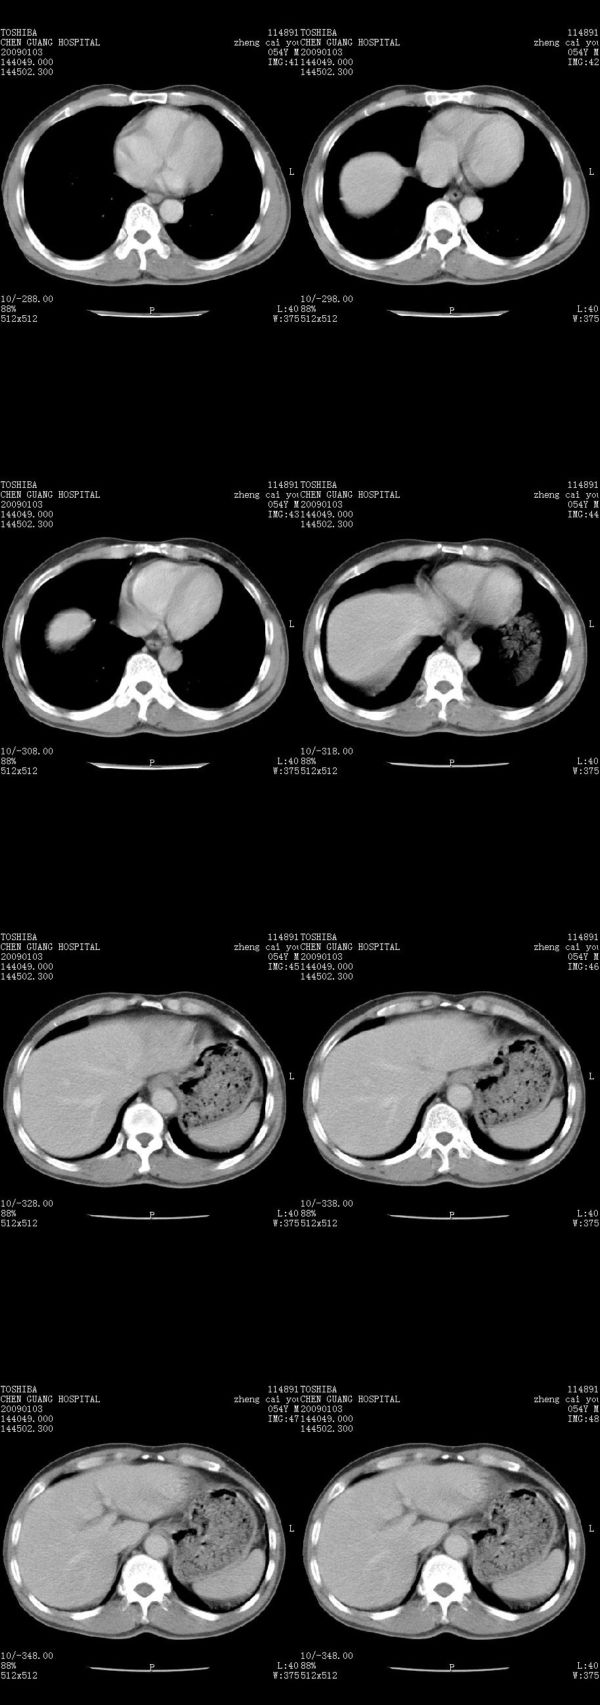

男,54岁,右侧胸部疼痛,平时吸烟,有抽烟后咳嗽咯痰史。昨天没把xiphoid软件吃懂,所以没把纵隔窗图像处理出来!请各位老师帮忙看一下右肺门有没有问题?谢谢!!!!!!!!!!

右肺上叶后段近气管旁仍可见一结节灶,不除外为肿大的淋巴结影。

我同学讲红线部分强化不好,感觉不是很舒服,这是什么道理?

我同学讲红线部分强化不好,感觉不是很舒服,应该 是软组织间隙,不是一个孤立的病灶。

气管前腔静脉后似见增大淋巴结影,肺门区未见明显肿块影。肺窗示右肺中叶外侧段透亮度增高,可过一段时间再查一下对比一下,毕竟是自己的至亲,又有条件,辐射就顾不得了。

也觉得还好吧,只是右下肺动脉显粗了点,纵膈有钙化淋巴结,再有肺窗就更好了

各位老师:奇静脉增宽,肺上未见明显实变,这还需注意观察些什么?????

右侧肺门影增大,不除外增大淋巴结可能